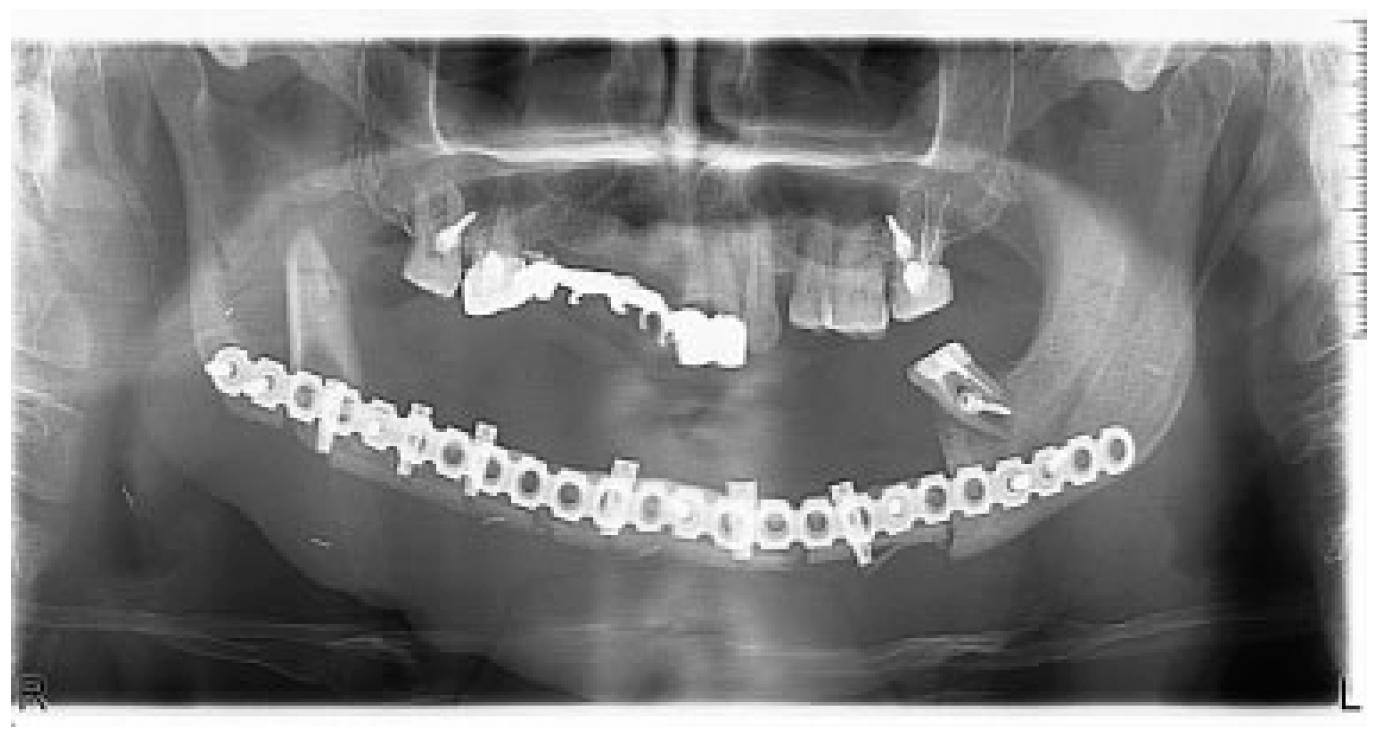

There were no significant complications postoperatively. Postoperative CT and OPG showed bone graft, dental implants, and reconstructive plate to be positioned in accurate anatomical relationship to each other and facial skeleton (Figure 8). A half year later, reconstructive plate was replaced by titanium miniplates (Figure 9).

At this stage, the facial appearance with new mandible does not show any significant changes (Figure 10a,b).

Figure 9. Reconstructive plate was replaced by miniplates.